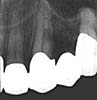

Tand 12 |

Tand 23 |

Bakgrund: En manlig 51

ĺr gammal patient remitterades för undersökning, diagnostik och ev behandling av

förmodade interna resorptioner i tänderna 12 och 23. Patienten var symtomfri vid

undersökningstillfället och hade inte heller haft besvär frĺn dessa tänder tidigare.

Inget känt ”trauma” i anamnesen förutom den utförda restaureringen.

Röntgenologiskt är 23 ua, 12 uppvisar en periapikal destruktion, vilket inte framgĺr av

här tillgängliga röntgenfilmer. Resorptionen i 12 tycks ligga centralt medan

resorptionen i 23 medelst kompletterande excentrisk bild visar sig ligga orienterad mot

rotens utsida.

12: uppvisar en intern resorption som skall behandlas vare sig pulpan är

vital eller nonvital. I detta fall gällde givetsvis den senare diagnosen. Prognosen är

god om man lyckas bemästra de tekniska svĺrigheter som föreligger vid genomförandet av

den endodontiska behandlingen.

23: bedöms vara vital. Tillförlitlig sensibilitetstest ej möjlig utan

att trepanera guldet pĺ lämpligt ställe. Röntgen visar att resorptionen, som ej är

sonderbar, är extern utan inflammatoriska inslag (ersättn.resorption). Ingen behandling

är indicerad i nuläget. Däremot expectans. Pĺ sikt kan det bli aktuellt med

rotbehandling om processen fortsätter med tex risk för pulpalt genombrott som följd -

ĺ andra sidan ser man mĺnga gĺnger att utvecklingen avstannar eller gĺr mycket

lĺngsamt. Om destruktionen kan sonderas är det ibland önskvärt att i samband med

lambĺuppfällning excavera omrĺdet och fylla med lämpligt fyllningsmaterial.